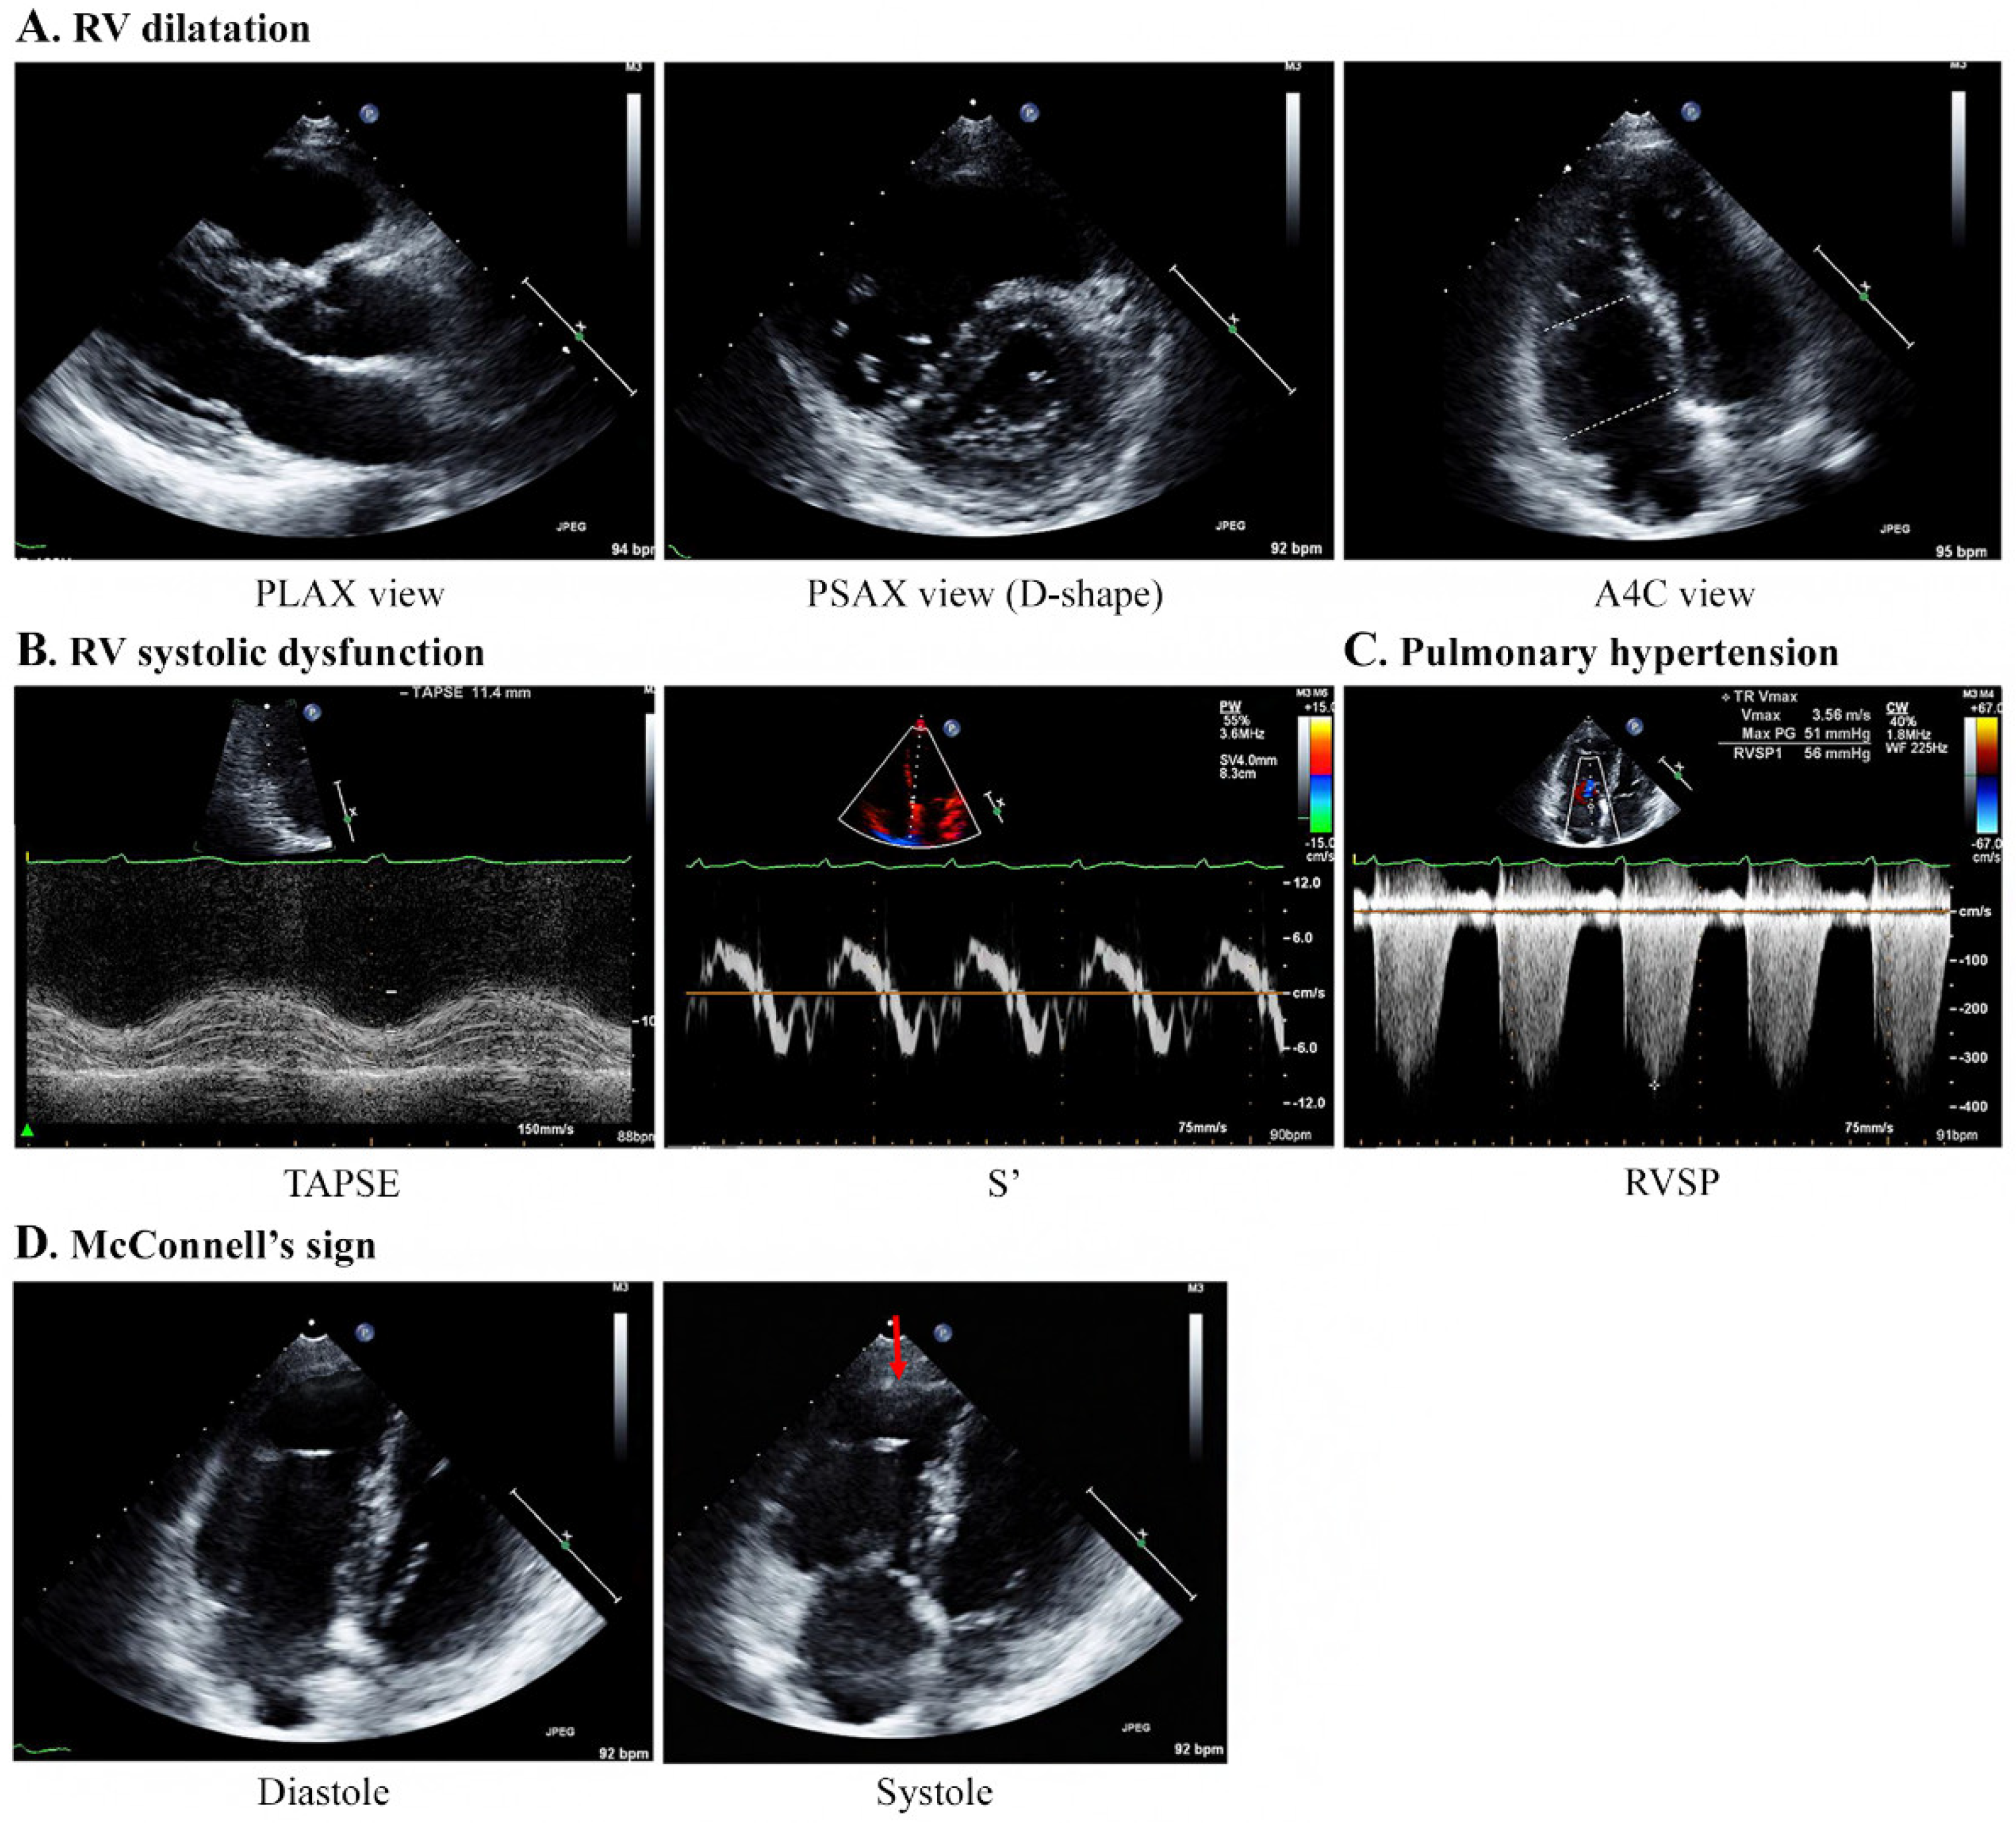

Echocardiography was performed by emergency physicians for all nine patients, and the characteristic findings are described in Table 3 and Figure 3. All patients showed moderate-to-severe RV dilatation with D-shaped LV on echocardiography (Supplementary Videos S1 and S2). The base and mid-RV median sizes (IQR) were 4.2 (4.2–4.5) cm and 3.4 (3.1–3.7) cm, respectively. The median TR Vmax (IQR) was 3.8 (3.5–3.8) m/s, and the median RVSP was 63 (58–79) mmHg, indicating severe PH. The median value of TAPSE (n = 7) was 15 (11–17) mm, showing a decrease in RV systolic function, with one patient having a normal value of 21 mm. The values of S’ (n = 4) ranged from 7.7 to 11.9 cm/s. Notably, five patients showed McConnell’s signs of RV dysfunction with a regional pattern of akinesia of the medial free wall, but normal motion at the apex (Supplementary Video S3). However, the LV size was normal in all patients, and the LV ejection fraction did not decrease significantly, ranging from 56% to 67%. The e/e′ values for LV diastolic dysfunction in four patients were within the normal range (5.7–8.9).

Figure 3.

Specific echocardiography features concerning patients with PTTM. A 40-year-old woman with breast cancer (Case 1). (A) Echocardiography results indicate RV dilatation with a D-shaped LV (mid/basal RV size: 29/40 mm). (B) TAPSE and S’ are 11.4 mm and 7.4 cm/s, respectively, indicating a decrease in RV systolic function. (C) The TR Vmax is 3.56 m/s, indicating PH. (D) McConnell’s sign, which is an akinesia of the RV mid-free wall except for the apex (red arrow), is observed. Abbreviations: A4C, apical 4 chamber; PLAX, parasternal long axis; PSAX, parasternal short-axis view; PTTM, pulmonary tumor thrombotic microangiopathy; RV, right ventricle; RVSP, right ventricular systolic pressure; S’, lateral tricuspid annulus peak systolic velocity on tissue Doppler imaging; TAPSE, tricuspid annular plane systolic excursion; TR V max, tricuspid regurgitation maximum velocity.

In this study, McConnell’s sign was observed in five patients. McConnell’s sign describes a regional pattern of acute RV dysfunction on echocardiography, which was first observed in a cohort of patients with acute PTE [23]. This sign refers to the coexistence of akinesia of the mid-to basal free RV wall with maintained apical contractility, as opposed to the global wall motion abnormalities seen in chronic RV failure [24,25]. Although it is unclear why McConnell’s sign is observed in patients with PTTM, it may be related to the phenomenon of PH associated with microscopic tumor embolism, similar to that seen in PTE. In this study, two patients with suspected PTE after demonstrating acute RV failure were found to have McConnell’s sign on echocardiography. However, after confirming the absence of visible PTE on chest CT, malignancy was suspected to be inversely related to the possibility of PTTM. The condition of these patients deteriorated rapidly and histological confirmation was not possible; however, PTTM was strongly suspected to be related to malignancy (ovarian cancer and metastasis of unknown origin). Therefore, when McConnell’s sign is newly observed in patients with cancer, our findings indicate that PTTM should be considered a differential diagnosis in the absence of PTE.